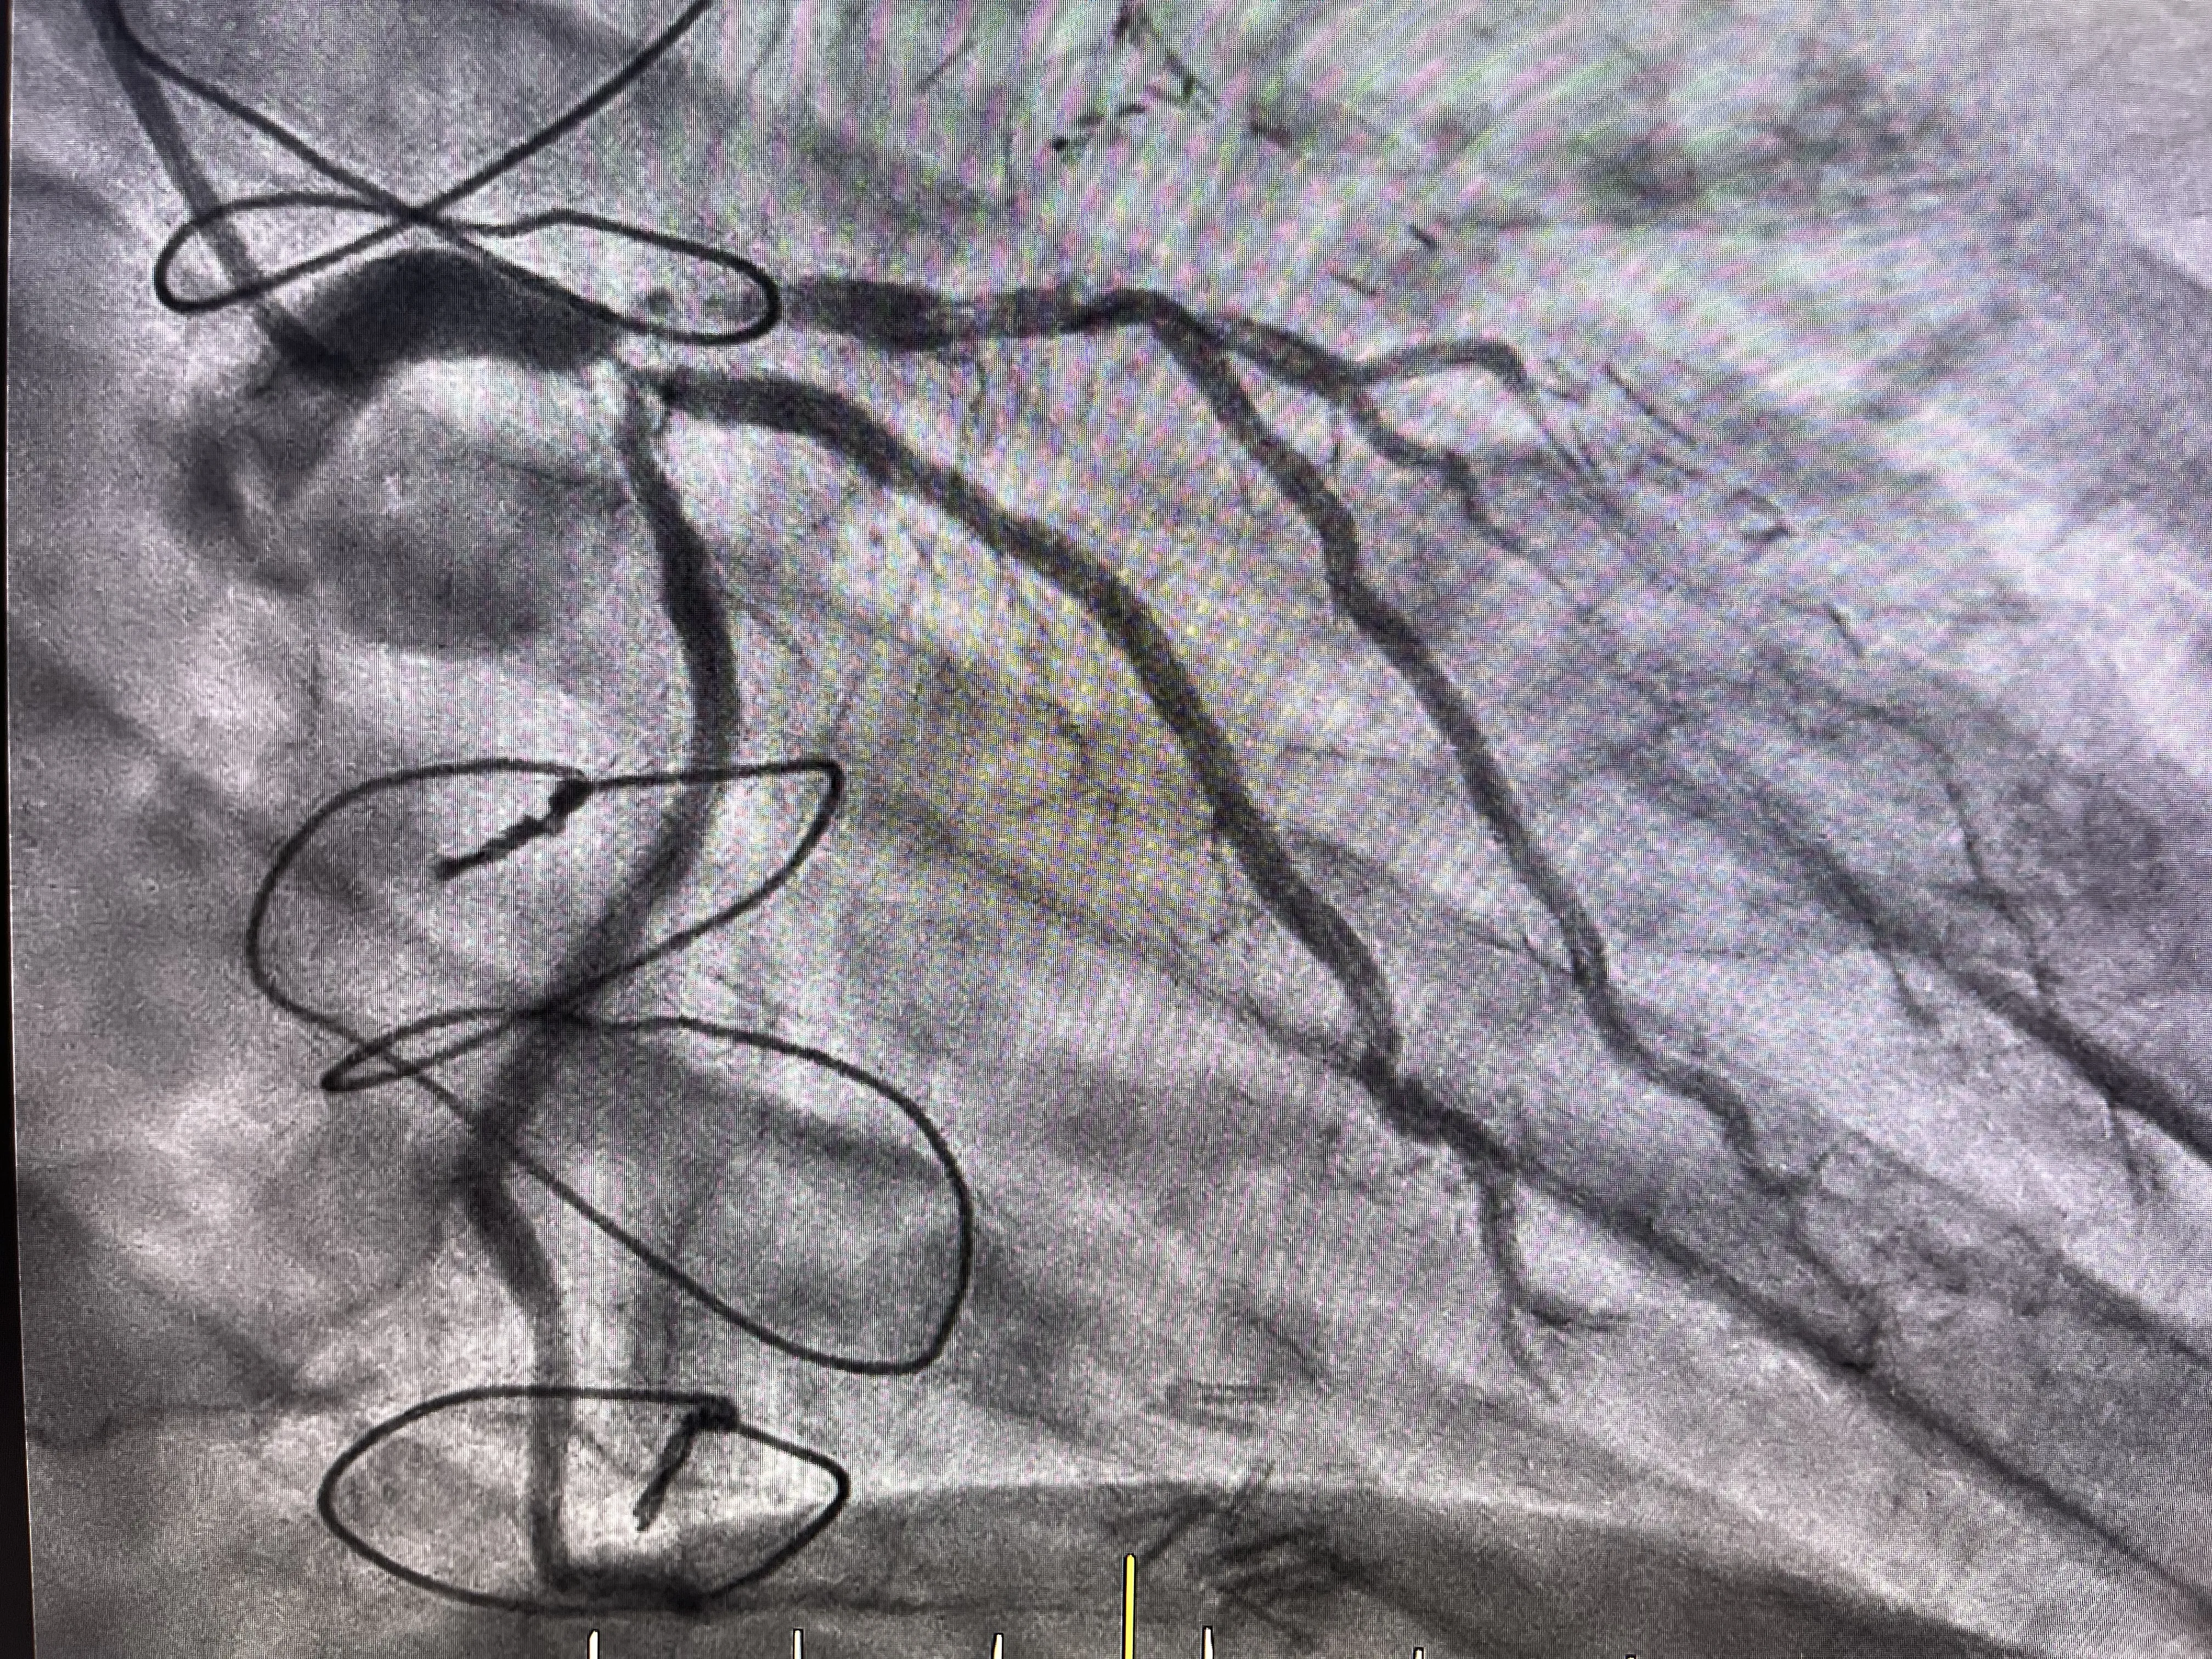

Evaluación del bypass en la angiografía

La angiografía realizada durante el cateterismo reveló que el bypass está en buen estado y cumple su función de irrigar la arteria descendente anterior. Este hallazgo es positivo, ya que indica que el bypass sigue siendo una vía efectiva para mantener el flujo sanguíneo al corazón, a pesar de las obstrucciones presentes en las arterias coronarias nativas.

En este caso, el bypass está funcionando adecuadamente y proporciona irrigación a la arteria descendente anterior de manera retrógrada. Esto significa que el flujo sanguíneo se dirige hacia atrás desde el bypass hacia la arteria, asegurando que el músculo cardíaco reciba el oxígeno y los nutrientes necesarios para su funcionamiento. Esta irrigación retrógrada es vital para mantener la viabilidad del tejido cardíaco, especialmente cuando la arteria original está obstruida.

En cuanto a la coronaria izquierda, se identificó que el ostium de la arteria circunfleja estaba a punto de obstruirse completamente. Además, la arteria descendente anterior estaba ya completamente bloqueada. Sin embargo, gracias al bypass previamente realizado, la descendente anterior está siendo irrigada adecuadamente, lo que mitiga el impacto de la obstrucción en el flujo sanguíneo al corazón.